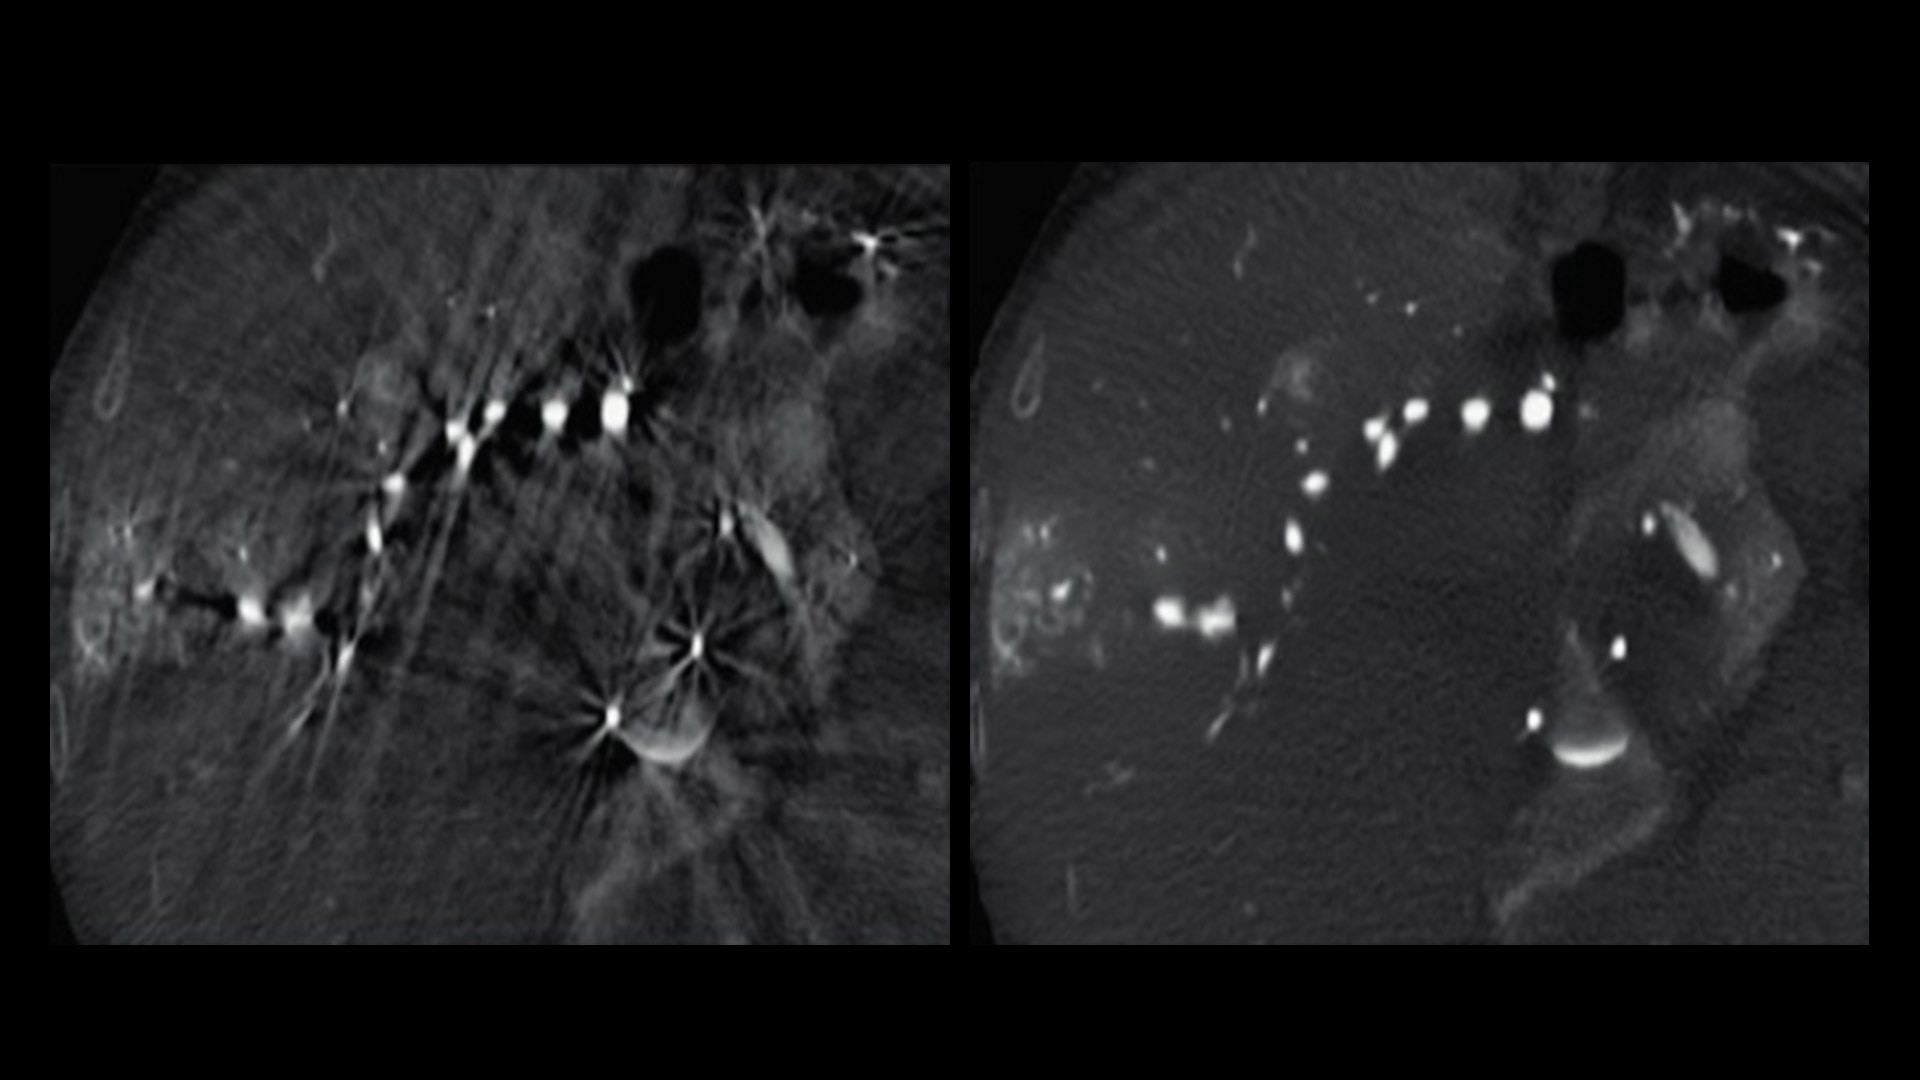

Effortless Recon DL

A portfolio of deep-learning applications designed to easily and quickly acquire and construct exceptionally clear images for confident decision making.

5. AIR Recon DL

AIR Recon DL leverages raw data and is integrated in the image reconstruction. This delivers improved SNR and sharper images by up to 60%.

6. Sonic DL

Versus full-sampled CINE acquisition.